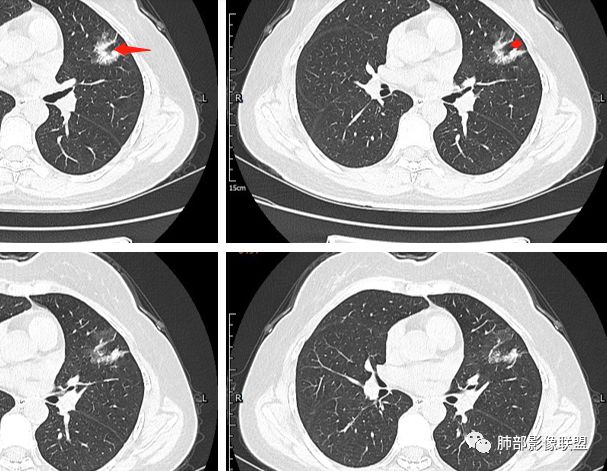

这有一个小结节

这是月牙铲吗?

分叶结节,内部结构杂乱,边缘板刷样毛刺,GGO边界清楚 医学百科网 | YxBaike.Com

胸膜牵拉

月牙铲? 医学百科网 | YxBaike.Com

常规要考虑腺癌 医学百科网 | YxBaike.Com

2.病灶的胸膜牵拉线与其间病灶胸膜侧的磨玻璃边构成朝向胸壁的“月牙铲”结构,这种影像学表现某种程度上反映出病理学特征——病灶收缩 小叶间隔阻挡。 医学百科网 | YxBaike.Com

二.关于胸膜下小结节: 医学百科网 | YxBaike.Com

结节影太小,尚未能够充分反映出影像学特征。随访观察应当是恰当的处置方式。

4 肺腺癌之—月牙铲 医学百科网 | YxBaike.Com

在影像上观察到肿块或磨玻璃结节一侧的内凹,像个月牙铲形态,病理是肿瘤生长受到小叶间隔阻挡并受肿瘤内部的收缩力形成,王兆宇老师称之为“月牙铲”!对诊断肺腺癌较有特异性。